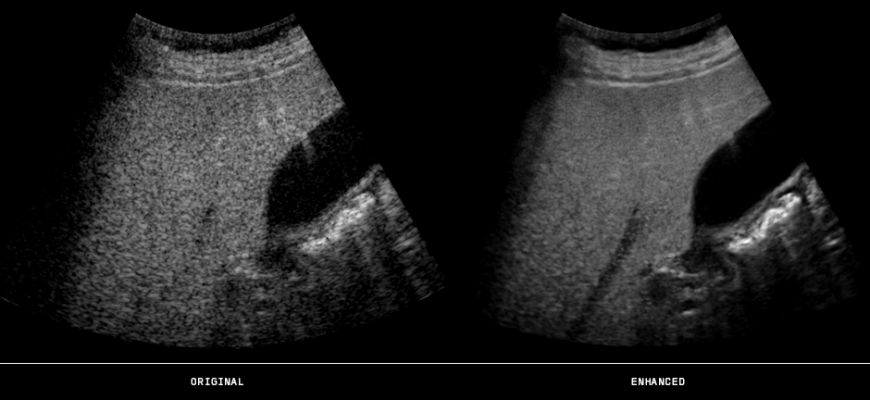

The PlusView software enhances ultrasound imaging with speckle reduction and edge-enhancement features. It also allows for deeper penetration, which could facilitate better ultrasound imaging of overweight patients